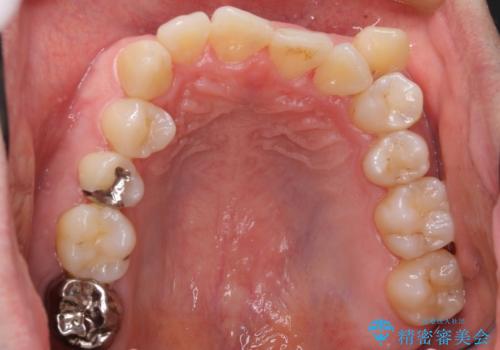

- 受け口を主訴に来院。

下あごが大きく、顎の手術を含めた矯正をおすすめしましたが、手術は怖いので絶対にしたくないとのことでした。

歯並びのみを治す矯正は難しく、長期にわたる治療になるとご説明しました。

かみしめもあり、骨も固く、歯根も長いためなかなか歯が動かず、患者様も治療する側も忍耐を要する長期戦となりました。